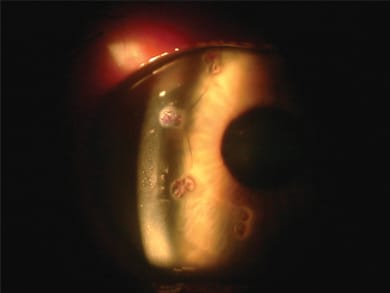

Also, I have found that some patients are wary of surgery because they have had perfect vision all their lives and they are not accustomed to the idea of having vision correction. Thus, surgeons can place just 8 CK spots with a large optical zone — which is usually 8 mm (Figure 2). This way, patients can be introduced to CK and have more treatment to refine their reading vision later as they want to. This "titration" is difficult to achieve with lasers, and I routinely use this application in my practice.

Figure 2. CK Retroillumination: For on-label CK, patients receive 8 spots at a 7-mm optical zone.